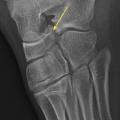

Certaines fractures non ou peu déplacées peuvent être de diagnostic difficile. La fracture de Tillaux touche préférentiellement les adolescentes en fin de croissance, avec une atteinte de l’extrémité distale et latérale de l’épiphyse tibiale. Le tableau clinique mime une entorse de cheville et le trait de fracture n’est pas toujours évident à la radiographie (fig. 3). La fracture étant articulaire, le scanner est souvent nécessaire pour décider d’une ostéosynthèse. Il faut également se méfier des fractures de la base du cinquième méta­tarsien, à ne pas confondre avec le noyau d’ossification secondaire. L’examen clinique permet donc d’orienter le diag­nostic, car la radiographie peut être trompeuse (fig. 4).